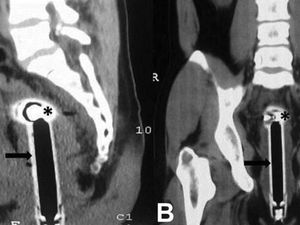

Seorang pria di Jember bikin heboh karena ada gelas di perutnya. Tidak benar-benar di perut alias lambung sih, menurut hasil pemindaian gelas itu ada di rektum.